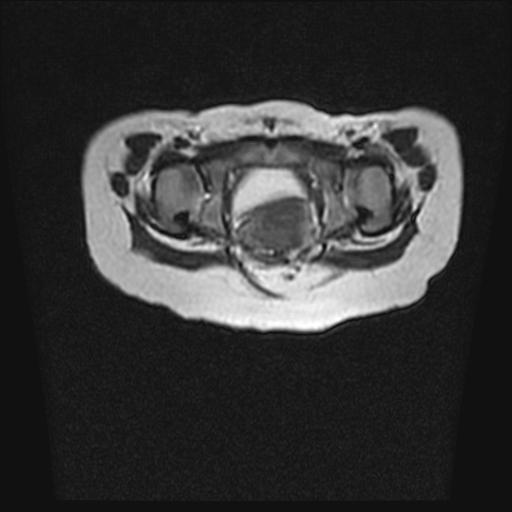

标题: PED0016:脊膜膨出 [打印本页]

标题: PED0016:脊膜膨出

四个月的女婴,ct示脊膜膨出.

脊柱裂、脊膜膨出,请结合临床除外皮毛窦。

脂肪脊髓脊膜膨出

脊柱裂、脊膜膨出